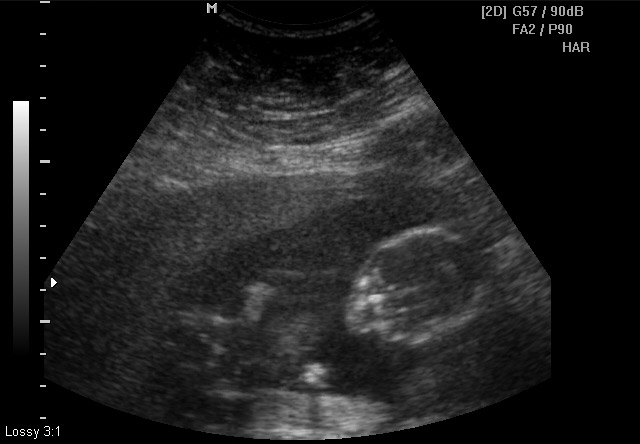

The ultrasound tech kept referring to the baby as "he/him"... but, they don't make gender determination until 18 weeks. Anything that can be gleaned from these?

Attachment 15430Attachment 15431Attachment 15432Attachment 15433Attachment 15434Attachment 15435